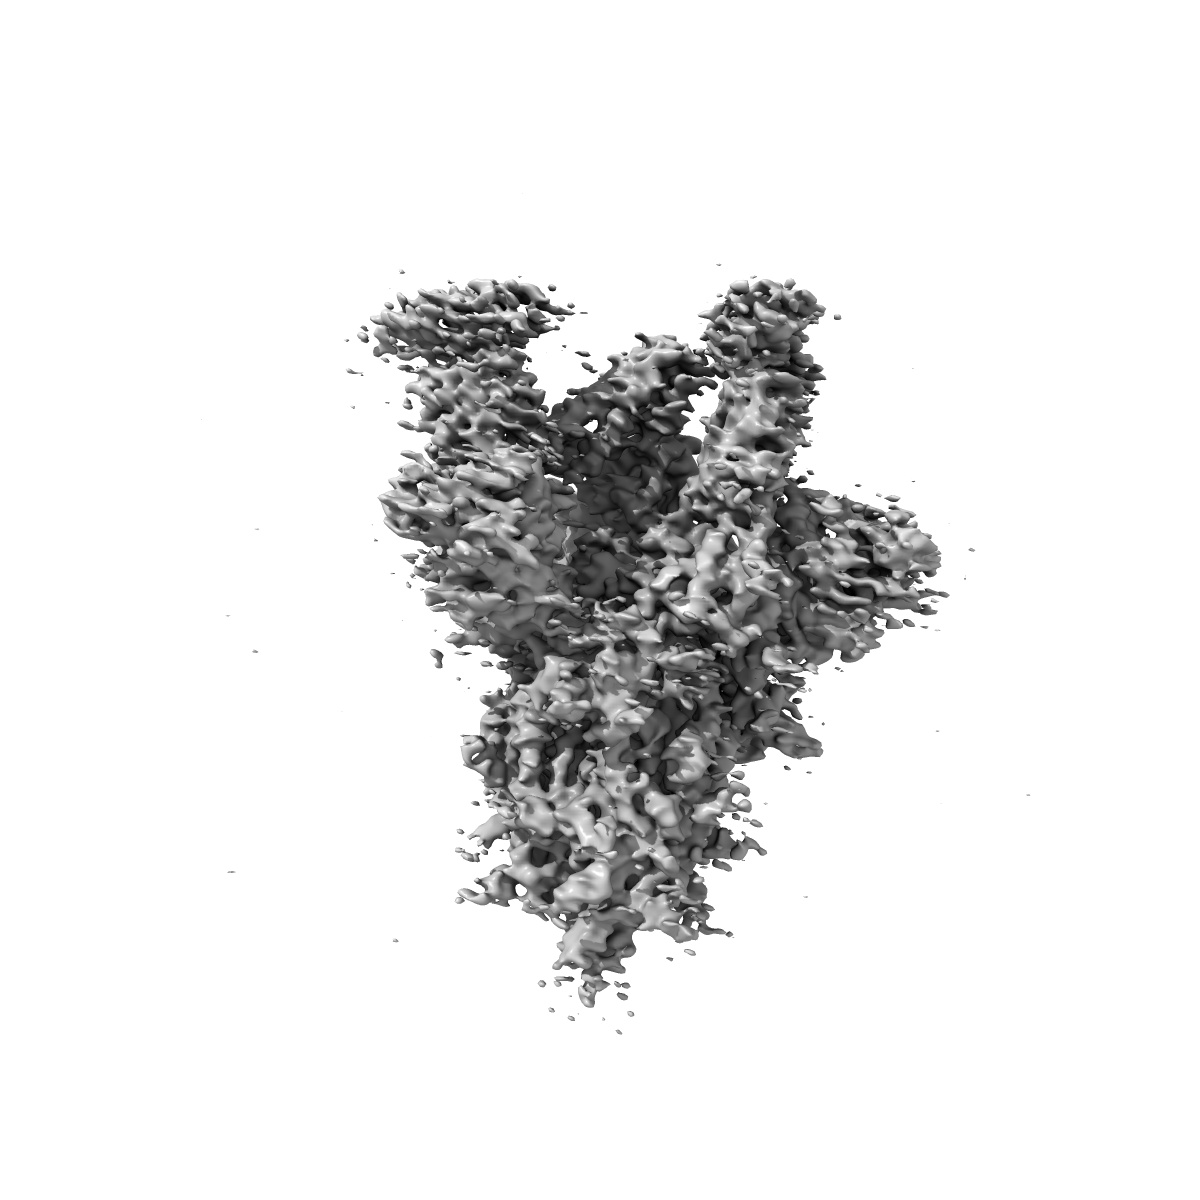

EMD-22916

Structure of the SARS-CoV-2 S 6P trimer in complex with the ACE2 protein decoy, CTC-445.2 (State 4)

Single-particle4.1 Å

Sample: Ternary complex of CTC445.2 inhibitor with SARS-CoV-2 S 6P glycoprotin